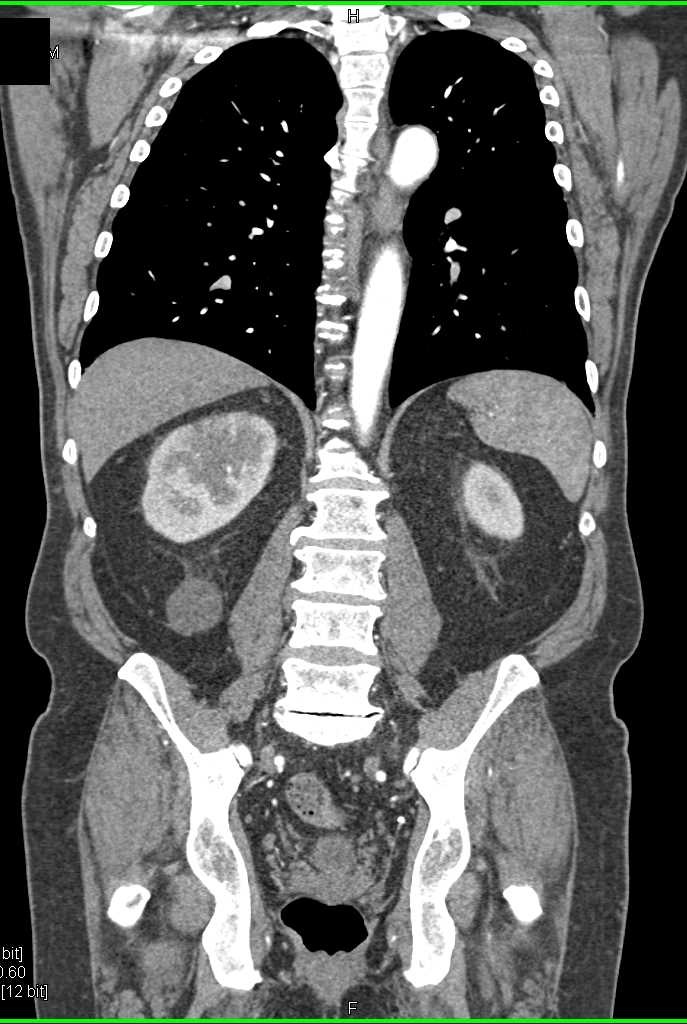

Acute Pyelonephritis Right Kidney